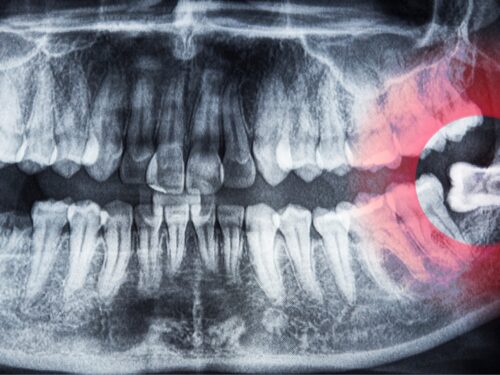

Zęby zatrzymane to zęby prawidłowo wykształcone pod względem anatomicznym, które jednak nie wyrżnęły się powyżej linii dziąseł. Dzieje się tak dlatego, że utknęły one w kości szczęki. Problem może dotyczyć każdego z zębów, zarówno górnych, jak i dolnych. Najczęściej jednak występuje w przypadku zębów mądrości. O zatrzymanym zębie mówimy, kiedy minęło co najmniej dwa lata od czasu, gdy powinien się prawidłowo wyrżnąć.

W każdym z tych przypadków może dojść zarówno do całkowitego, jak i częściowego zatrzymania wyrzynania się zębów. W pierwszym przypadku ząb jest niewidoczny w jamie ustnej, ponieważ całkowicie tkwi w kości. Wówczas możesz nawet nie wiedzieć o tym, że doszło do zatrzymania procesu wyrzynania zęba. Ujawnić to może dopiero wykonanie zdjęcia RTG szczęki. W drugim przypadku ząb może być pokryty jedynie błoną śluzową dziąsła lub delikatnie z niego wystawać. Widoczne są wówczas na przykład pojedyncze guzki zęba lub jedynie niewielki fragment jego korony.

Pierwszym i podstawowym krokiem w leczeniu zębów zatrzymanych jest ich prawidłowe zdiagnozowanie. W tym celu konieczne jest wykonanie badań obrazowych, aby określić dokładne położenie zęba, przyczynę zatrzymania wyrzynania oraz jego stopień. W zależności od przyczyny oraz stopnia zaawansowania problemu lekarz stomatolog wdroży odpowiedni plan leczenia.